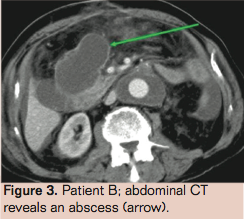

Patient A is a 78-year-old male with a history of Billroth 1 gastric resection, coronary artery bypass grafting, lung carcinoma (T1N0M0 treated with radiotherapy), a venous supragenual femoral-popliteal bypass, percutaneous transluminal angioplasty, chronic obstructive pulmonary disease GOLD 2, hypertension, and hypercholesterolemia. He presented with a ruptured aneurysm of the abdominal aorta with a diameter of 7.0 cm on computed tomography (CT) angiography with no signs of infection or inflammation. Emergency open aneurysm repair was performed with a Dacron prosthesis (DuPont). After surgery, he was admitted to the intensive care unit (ICU) for 2 days where he developed pneumonia (Escherichia coli), which was treated with ceftriaxone, a broad-spectrum cephalosporin. At return to the vascular surgical ward, fever persisted. Common postoperative causes of infection were ruled out. CT angiography showed intraperitoneal and retroperitoneal abscesses (Figure 1). CT-guided puncture of only the periprosthetic hematoma was performed. The other abscesses were not punctured and drained. Culture revealed a Listeria monocytogenes. Although L monocytogenes infection is commonly seen in patients with close contact to milk and cheese products, our patient had no history of eating or working with these products. The graft infection was discovered 2 weeks after initial operation, and was considered an unfavorable period for a relaparotomy. We believed graft removal was not feasible in this patient because of his poor nutritional status, recent pneumonia and recent postoperative status. Therefore we started conservative treatment. Antibiotics were switched to amoxicillin and gentamicin, according to sensitivity of the cultured micro-organism and administered intravenously during 6 subsequent weeks. Control abdominal CT showed a reduction of the abscesses (Figure 2). Blood levels of C-reactive protein (CRP) returned toward a normal value of 6 mg/L. The patient was discharged after a hospital stay of 61 days, with continuation of amoxicillin by mouth. An abdominal CT scan 15 months after discharge showed no signs of infection.